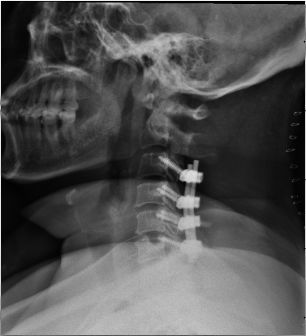

病例41:强直性脊柱炎患者合并脊髓型颈椎病怎

288x517 - 55KB - JPEG